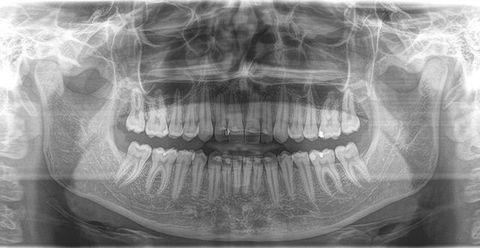

ContattiLa tua salute è al centro dell’impegno quotidiano dello Studio Braconi a Terni che, per garantirti servizi diagnostici tempestivi e precisi, si avvale esclusivamente delle migliori strumentazioni presenti sul mercato, come il nuovissimo Orthophos SL 2D: si tratta di un apparecchio specifico per l’analisi ortodontica, composto da due innovazioni, il Sharp Layer e il sensore DCS. Qui, con tempi di attesa ridotti, potrai usufruire di una qualità dell’immagine senza precedenti, dove la nitidezza è garantita anche nella valutazione dei casi più complessi e l’emissione delle radiazioni è sempre bassissima.

L’obiettivo dell’analisi è quello di valutare lo stato della bocca prima di eseguire un qualsiasi trattamento odontoiatrico, andando a evidenziare eventuali lesioni ossee, infiammatorie o cistiche; analizzare lo stato di salute della dentizione, soprattutto nelle fasi di sviluppo; tenere sotto controllo eventuali malformazioni o constatare la presenza di neoplasie mascellari o mandibolari.